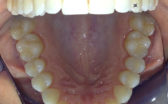

- After

At the end of four months, my front teeth were straight and I was able to have my braces removed! I am extremely happy with my Cfast end result and it was all worth it.